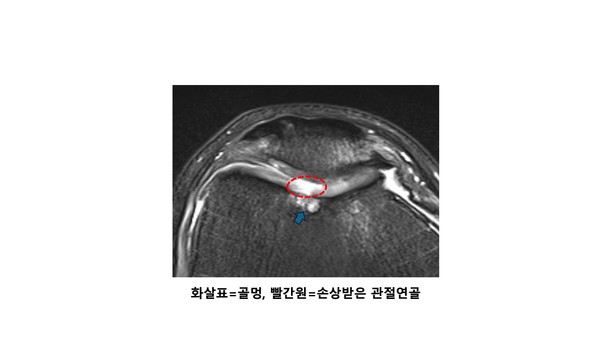

사진에서 보시는 것처럼 골멍이 잘 발생하는 부위는 관절 주위입니다. 뼈의 특성상 관절이 아닌 팔다리의 중간의 뼈는 피질골이라고 하여 쇠파이프처럼 주위가 아주 단단한 무기질로 둘러 쌓여있어 외부에 대한 충격을 모두 막아줍니다. 그러나 관절주위 뼈는 피를 생성하는 골수(bone marrow)가 위치하기 때문에 상대적으로 부드러운 해면골로 구성되어 있습니다. 이 부분은 피질골이 없기 때문에 관절에 대한 충격은 관절연골이 흡수해 주고 있습니다.

정상적인 외력 이상이 발생하게 되는 경우, 즉 연골이 흡수하기 못하는 크기의 외력이 발생하게 되면 해면골에 충격이 가게 되는데 이러한 경우 골멍 (bone bruise)가 발생하게 됩니다.

세번째는 어깨 탈구나 십자인대 손상처럼 관절의 탈구가 일어나 뼈가 어긋나면서 발생하게 되는 비정상적인 뼈의 충돌입니다. 관절 주위 뼈에 안정성을 부여해주는 인대가 손상이 되면 순간적으로 뼈의 위치관계가 어긋나게 됩니다. 그렇게 되면 비정상적인 충돌이 발생하면서 다시 본래의 자리를 찾아가게 되는데요, 이 충돌과정에서 뼈에 타박상, 즉 골멍이 발생할 수 있습니다.